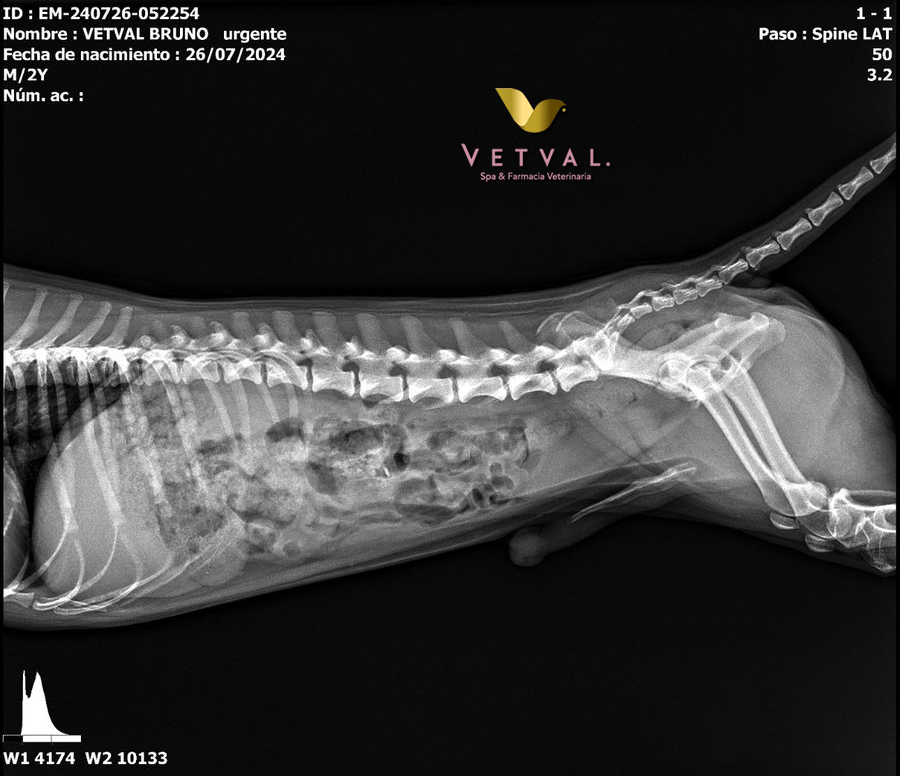

Consultas

Revisión de la salud de un animal para detectar problemas o enfermedades, y establecer un plan de tratamiento.